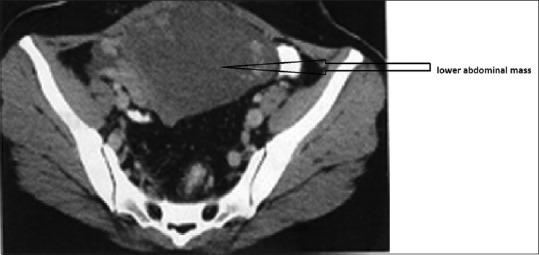

Choriocarcinoma is the most malignant tumour of gestational trophoblastic origin. Most ovarian choriocarcinomas are gestational in origin and usually metastasize to the ovary from uterine or tubal choriocarcinoma. Non gestational choriocarcinoma (NGOC) of the ovary is exceedingly rare and usually seen along with other germ cell tumors. Non gestational choriocarcinoma has been found to be resistant to single-agent chemotherapy and has a worse prognosis than gestational choriocarcinoma. We are reporting long term follow up of published rare case of pure non gestational ovarian choriocarcinoma (NGOC) with concurrent metastases to the spleen and adrenal glands, who developed a delayed solitary brain metastases, two years after completion of primary treatment. Surgery along with triple agent chemotherapy and radiotherapy was found to give good remission in this aggressive disease.

绒毛膜癌是起源于妊娠滋养细胞的最恶性肿瘤。大多数卵巢绒毛膜癌起源于妊娠,通常从子宫或输卵管绒毛膜癌转移至卵巢。卵巢非妊娠性绒毛膜癌(NGOC)极为罕见,通常与其他生殖细胞肿瘤同时出现。已发现非妊娠性绒毛膜癌对单药化疗耐药,且预后比妊娠性绒毛膜癌更差。我们报告了一例已发表的罕见的纯非妊娠性卵巢绒毛膜癌(NGOC)并伴有脾脏和肾上腺转移的长期随访病例,该患者在完成初始治疗两年后出现了延迟性孤立性脑转移。手术联合三联化疗和放疗在这种侵袭性疾病中取得了良好的缓解效果。